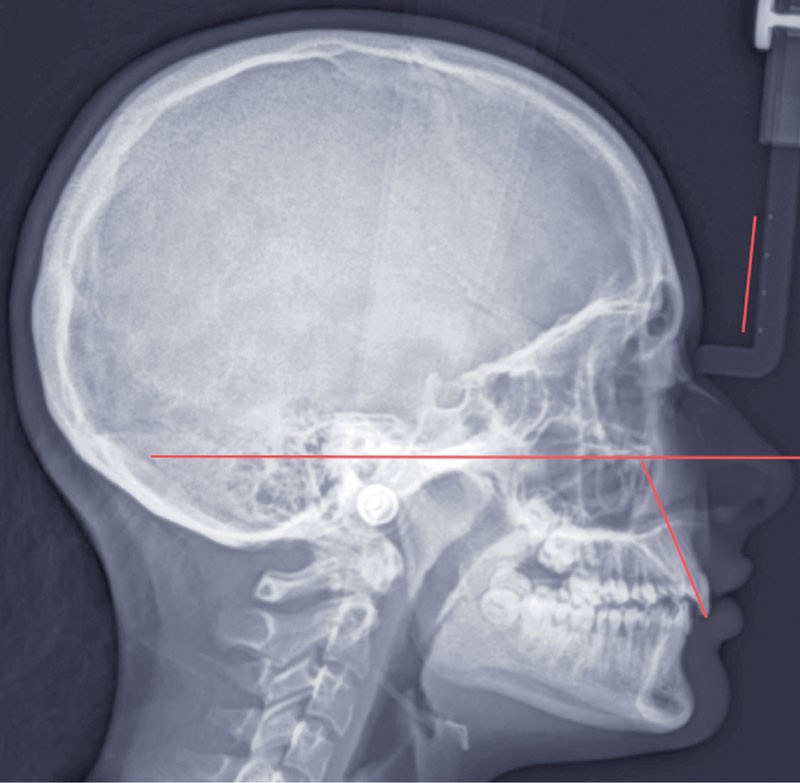

Son profil naso-mentonnier fin et très harmonieux traduit un équilibre squelettique tant antéro-postérieur que vertical (Classe I squelettique mésodivergente à tendance hypodivergente).

La téléradiographie de début de traitement à 11 ans et demi confirme une évolution en classe I squelettique hypodivergente (fig. 3).